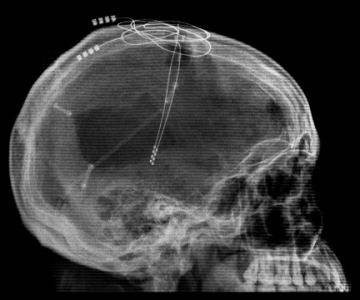

This X-ray image shows the electrodes that were placed in the head of a brain-injured man, allowing him to talk, eat, and move again.

| The Cleveland Clinic |

During a 10-hour operation, neurosurgeon Ali Rezai put two devices called electrodes deep within the center of patient’s brain, in an area called the thalamus.

Electrodes transmit electric currents. Rezai and colleagues proposed that transmitting currents deep in the brain would make the thalamus more active. And firing up the thalamus, they suspected, would wake up the whole brain.